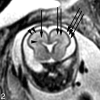

Fetal MR imaging is an increasingly available technique used to evaluate the fetal brain and spine. This is made possible by recent advances in technology, such as rapid pulse sequences, parallel imaging and advances in coil design. This provides a unique opportunity to evaluate processes that cannot be approached by any other current imaging technique and affords a unique opportunity for studying in vivo brain development and early diagnosis of congenital abnormalities inadequately visualized or undetectable by prenatal sonography. This 2-part review summarizes some of the latest developments in MR imaging of the fetal brain and spine and its application to prenatal diagnosis. This first part discusses the utility, safety, and technical aspects of fetal MR imaging, the appearance of normal fetal brain development, and the role of fetal MR imaging in the evaluation of fetal ventriculomegaly. The second part focuses on additional clinical applications of fetal MR imaging, including suspected abnormalities of the corpus callosum, malformations of cortical development, and spine abnormalities.